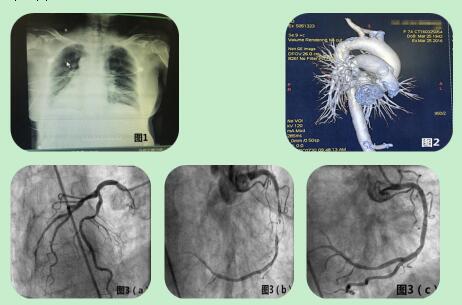

右位心合并心肌梗死一例

666x621 - 35KB - JPEG

病例丨右位心+急性心梗,这种技术不可少

830x502 - 925KB - PNG

右位心合并急性心肌梗死病例报告

462x305 - 22KB - JPEG